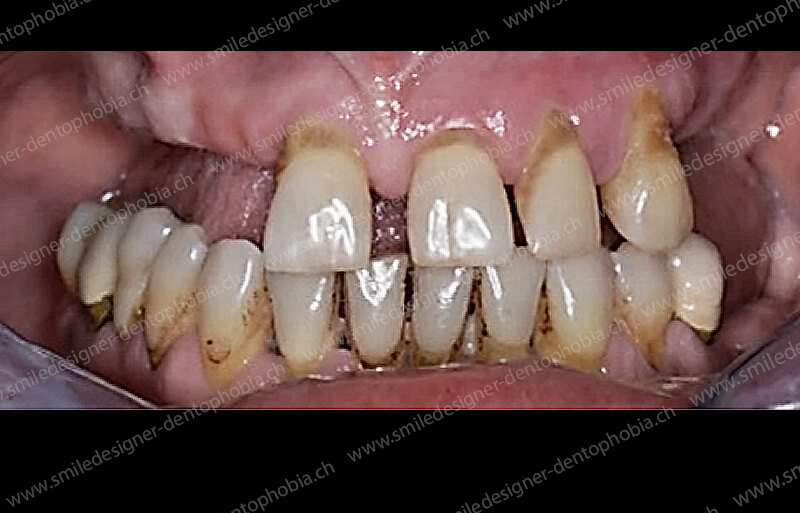

Cas clinique « DAMAGE CONTROL MCI » maxillaire : Bridge implanto-porté avec extensions postérieures (ALL ON 8). Version définitive des bridges avec un cosmétique en céramique.